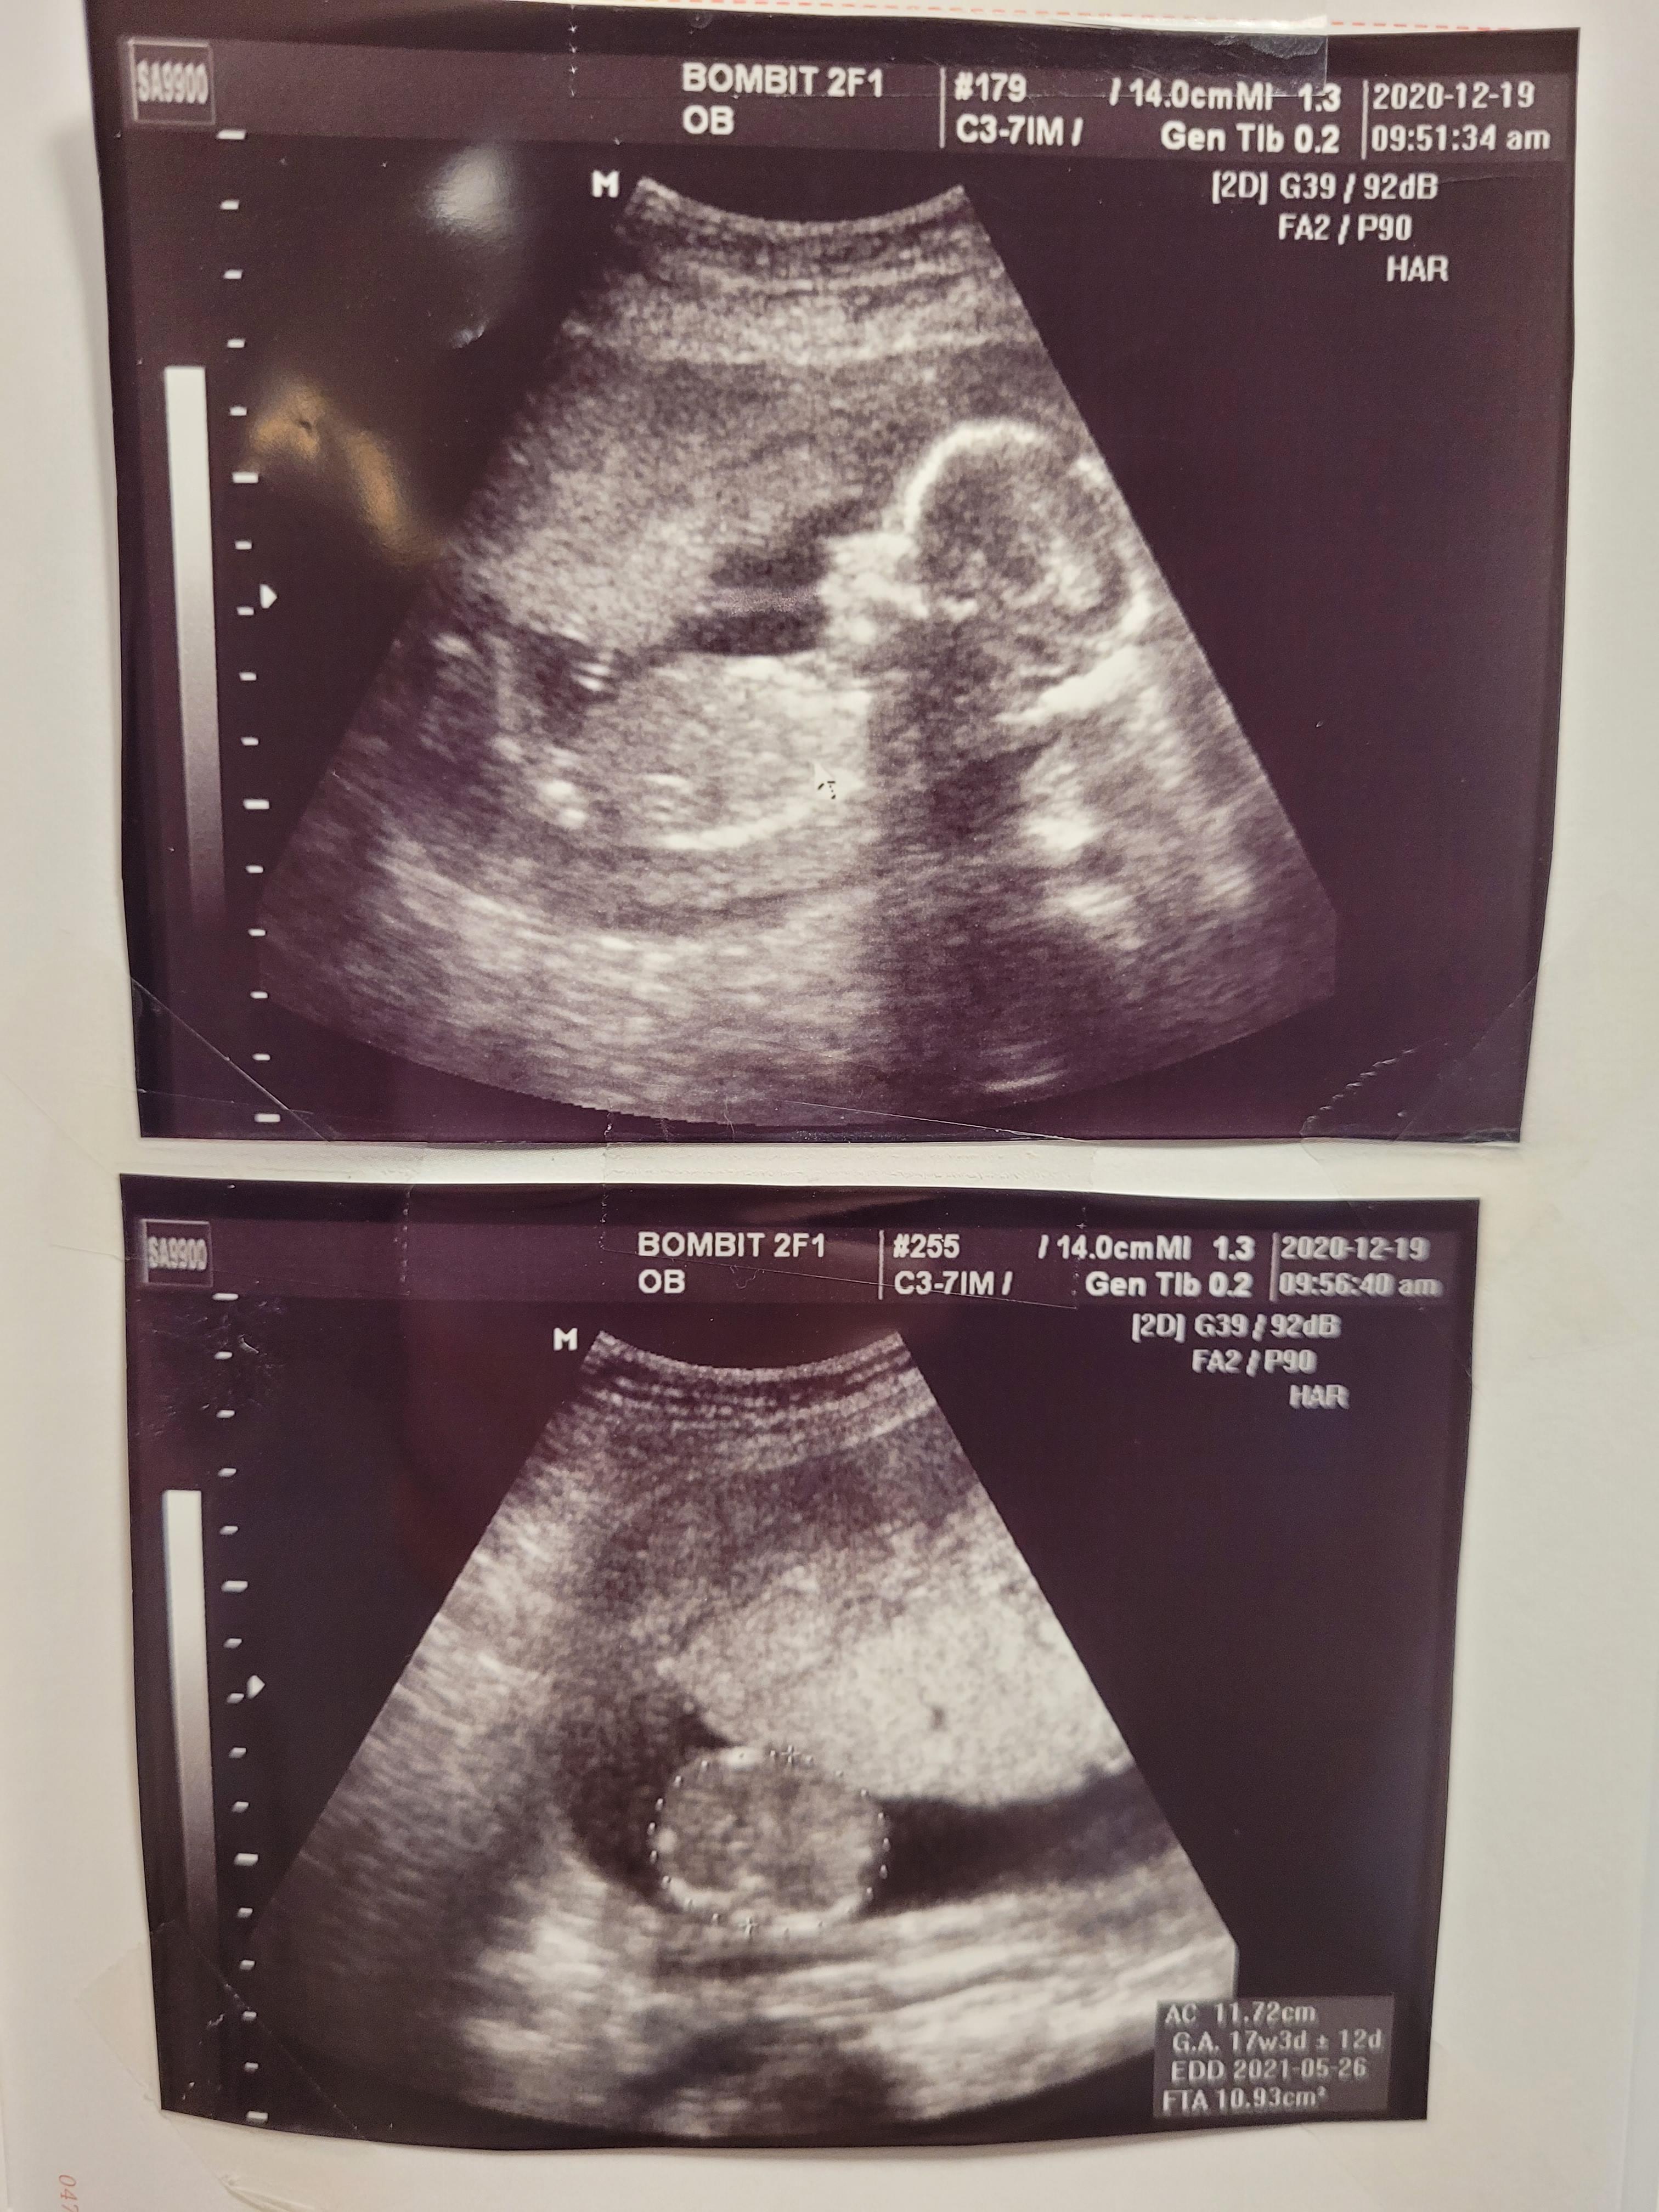

초음파로 태아 상태부터 확인합니다.

16주 0일인데, 17주 5일 크기까지 커버린 우리 행복이 ㅎㅎ

쑥쑥 잘 자라주고있어요

배둘레, 머리둘레 모두 주수보다 잘 자라주어서 뿌듯했어요

아무 이상도 없고 건강하게 잘 크고있네요^^